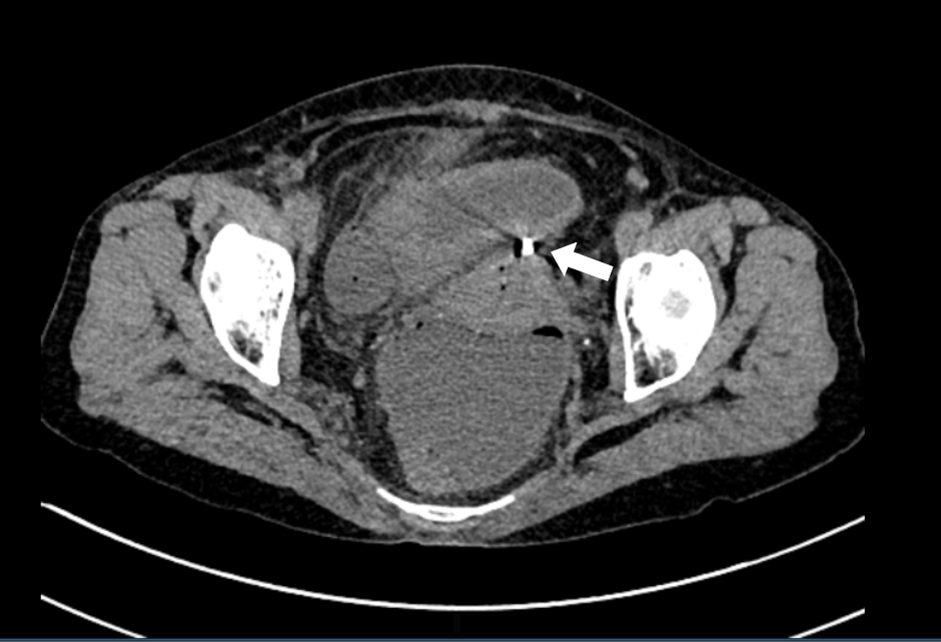

Hình ảnh chụp cắt lớp vi tính cho thấy dụng cụ tử cung xuyên qua thành tử cung vào ruột (mũi tên trắng).

Tại bệnh viện, bệnh nhân được chỉ định siêu âm ổ bụng, chụp cắt lớp. Kết quả, hình ảnh dịch khí tự do trong ổ bụng, tắc ruột cơ năng, dày thành ruột vị trí hố chậu phải và có dị vật đâm xuyên thủng đáy tử cung.